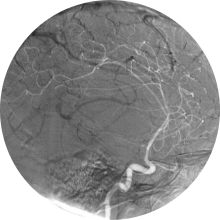

NeurofisiólogoEn el TAC CRANEAL, sin y con contraste, se observa un gran proceso expansivo intracerebral a nivel fronto-temporal derecho con zonas quísticas...